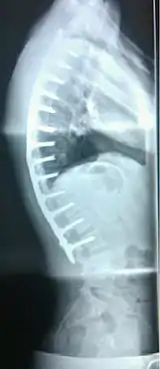

![]() | |

| Scheuermann's disease on lateral Xray of the T spine | |

| Diagnostic method | X-ray, MRI |

Diagnosis is typically by medical imaging. The degree of kyphosis can be measured by Cobb's angle and sagittal balance.